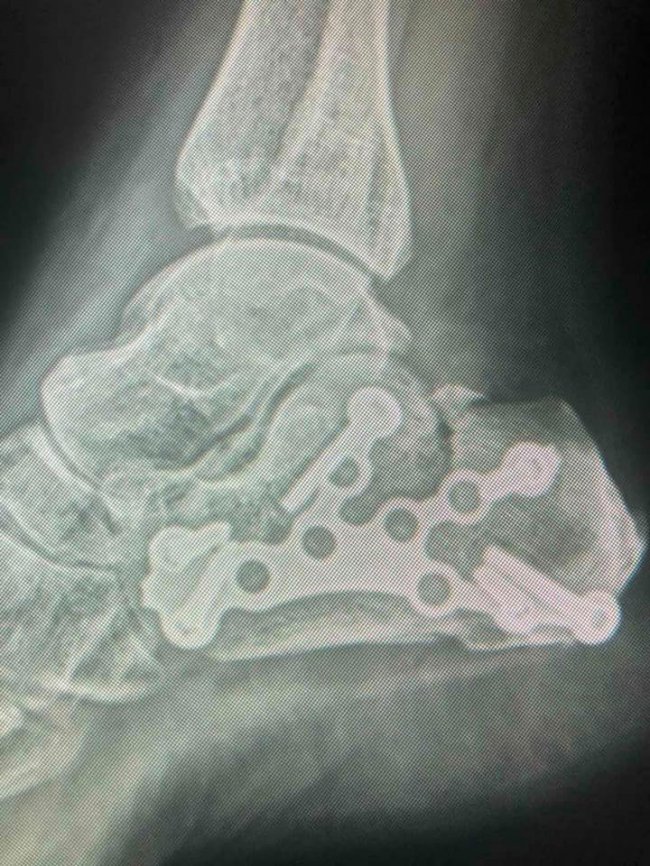

Після проведеного обстеження пацієнтки встановили діагноз:

відламковий перелом п‘яткової кістки зі зміщенням.

Під СМА (спинно-мозкова анестезія) провели остеосинтез п‘яткової кістки. Операція пройшла успішно. У пацієнтки були відновлені активні рухи в суглобах стопи.